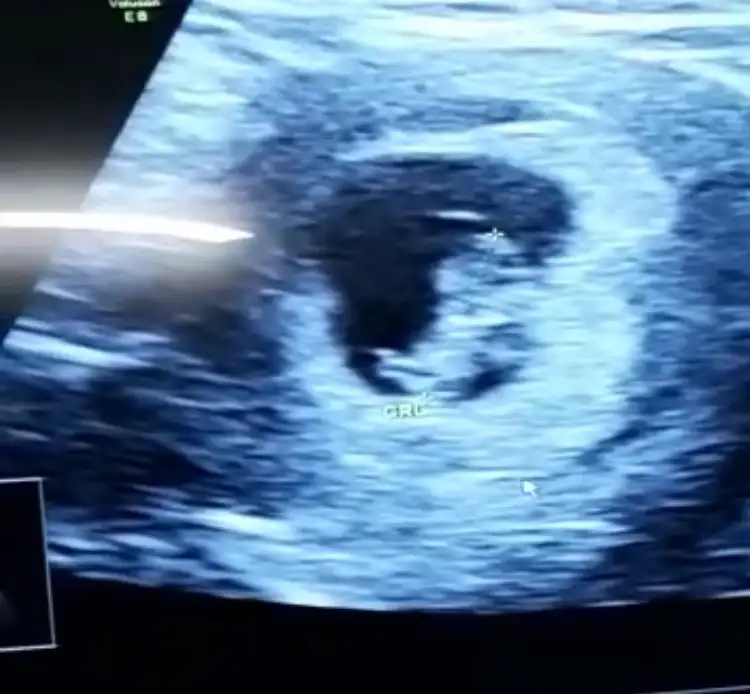

Bence erkek gibiEki Görüntüle 2277371 Buda arkadaşımın bebişi acaba onun Cinsiyeti nedir

9+4 göre erken sekil almış erkek diyorumBende yorum alabilir miyimEki Görüntüle 2218569